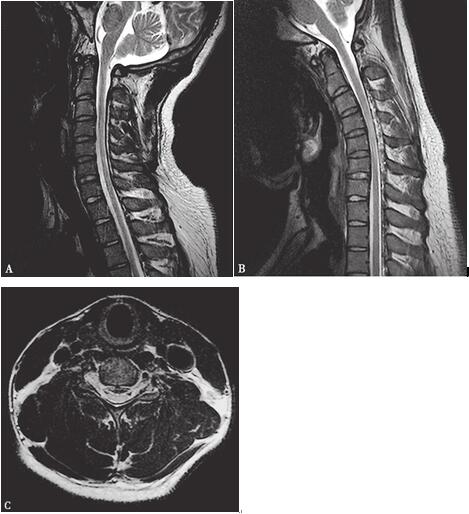

过屈过伸位颈椎MRI:颈椎顺列规则,生理曲度存在,各椎间隙无变窄,椎间盘无突出,C4~7脊髓内见斑片状及条状T2WI高信号,T1WI低信号影;过屈位显示C4~7水平硬脊膜后壁前移,硬脊膜后壁与椎管后壁间隙增宽,其内有迂曲走行血管影;轴位显示颈髓变扁。印象:考虑平山病(图34-1)。

图34-1 颈椎MRI的T2WI像:(A)矢状过伸位显示:C4~7水平椎管前后径变窄,髓内有异常T2高信号;(B)矢状过屈位显示:C4~7水平硬脊膜后壁前移,硬脊膜后壁与椎管后壁间隙增宽,其内有迂曲走行血管影;(C)轴位显示:C5~6水平脊髓受压、变扁,髓内有异常T2高信号。